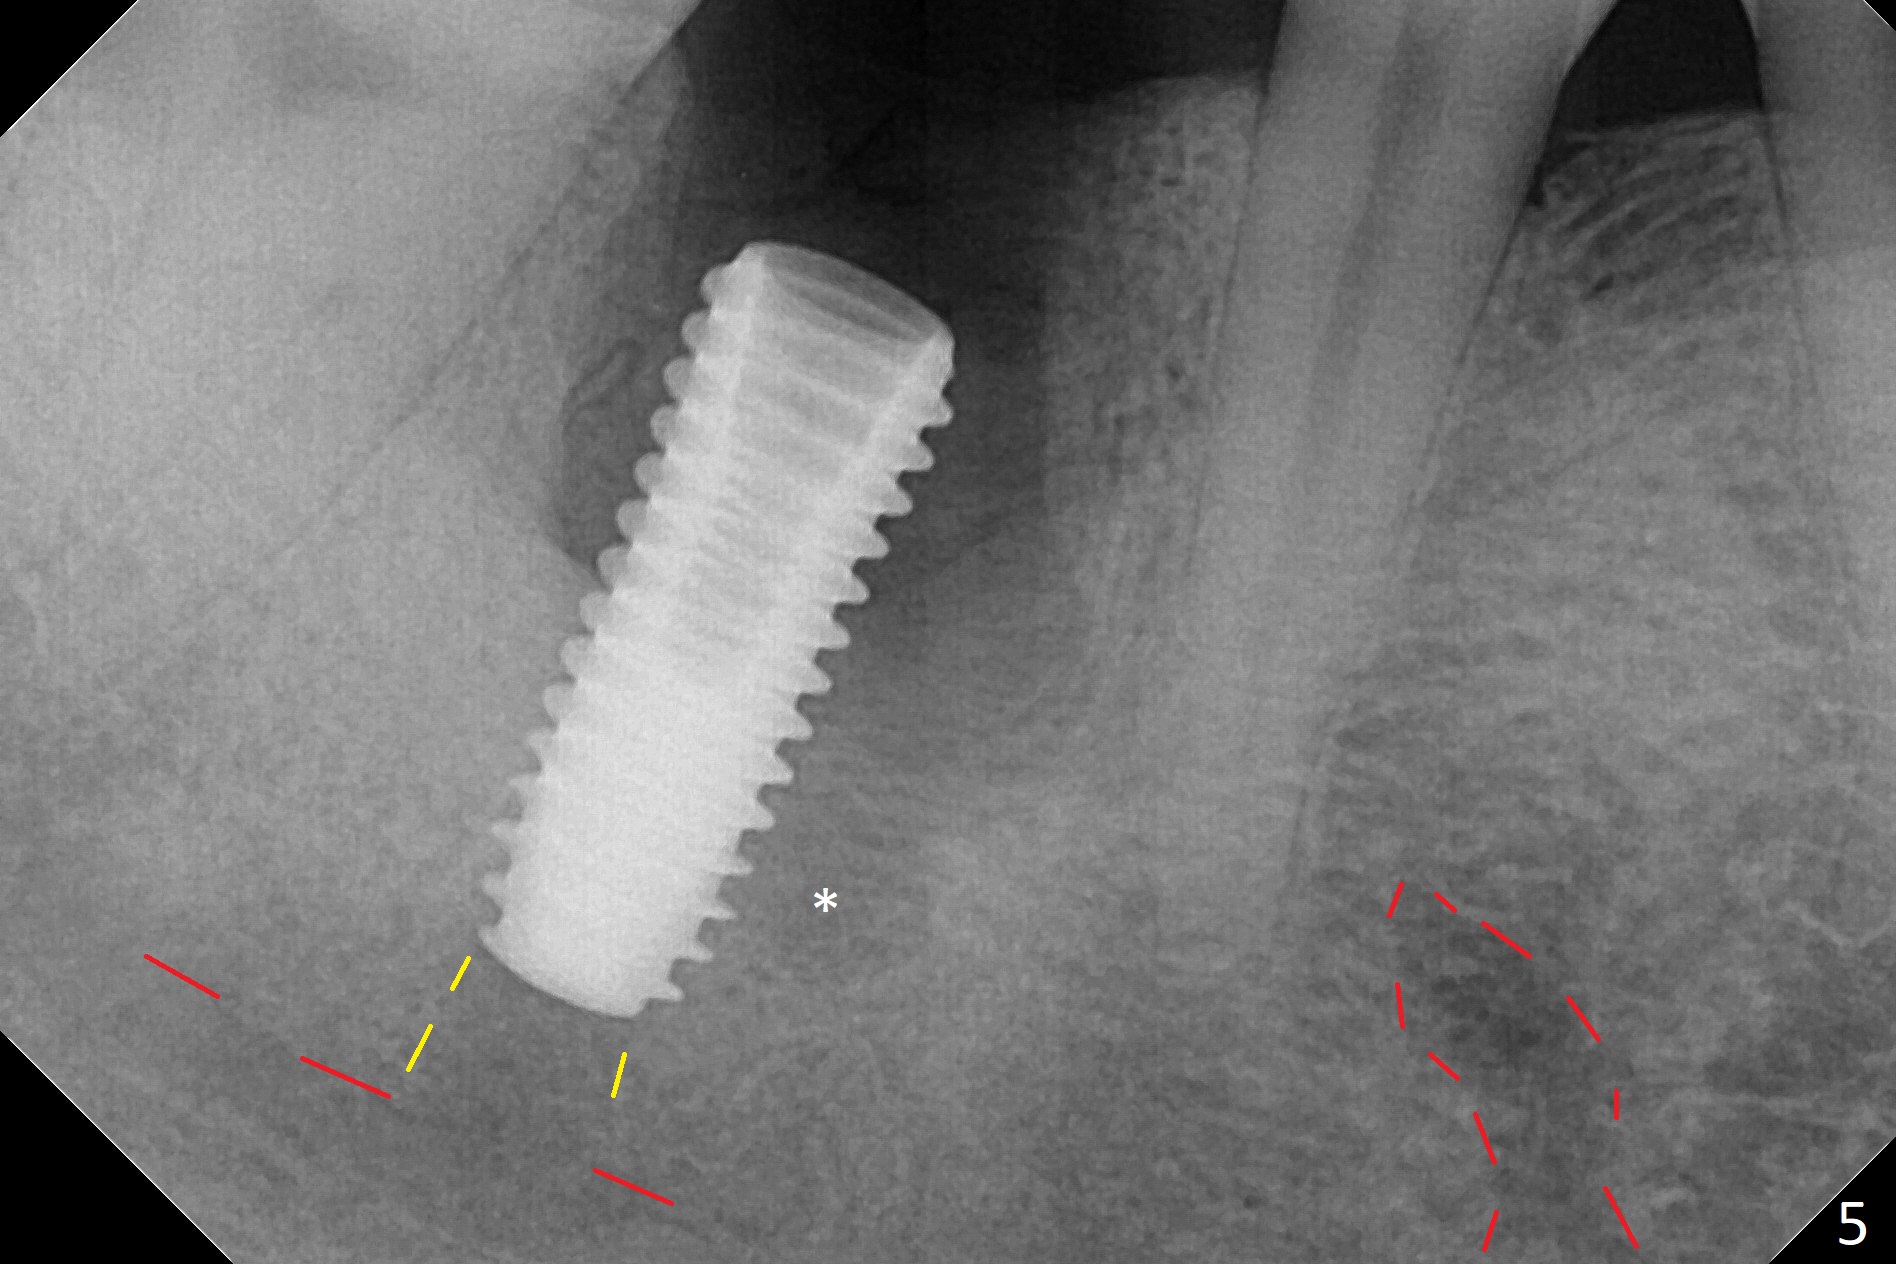

After the tooth #30 is extracted, the socket is 18 mm deep and the lingual plate is 4 mm tall. With hemorrhage, visibility of the socket, especially the bottom, is poor. The septum is almost completely defective. Following removal of the most buccal portion of the septum, osteotomy is initiated as buccal as possible, but it is mesial (Fig.1). In spite of effort to move the osteotomy distal, the osteotomy remains mesial and superficial (Fig.2 with 5 mm tap drill). Pain control is poor with infiltration. It appears that the smaller osteotomy (Fig.2 yellow line) may have extended close to the superior border of the Inferior Alveolar Canal (red line). It appears that there is 8.5 mm bone distal with ~ 2 mm clearance. After mandibular block, a new osteotomy is made distal; when a 3.8 mm drill is being used, there is hemorrhage from the osteotomy with apparent violation of the Canal integrity (Fig.3,4). But hemostasis is achieved with gauze pressure. A 5x13 mm implant is placed superficially (Fig.5) with a trace of the previous osteotomy (yellow line) and deep space created by the mesial osteotomy (*). Apparently the pathological and iatrogenic defects are filled with allograft (Fig.6 *). Guided surgery could have avoided the mesial osteotomy.